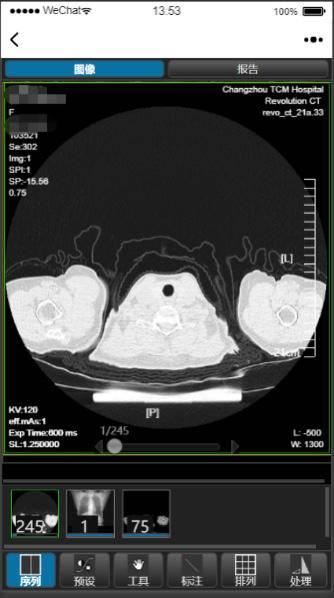

扬子晚报网4月9日讯(通讯员 王唯 采访人员 张斌)“云影像”通俗地说就是没有胶片 , 能够通过手机 , ipad等智能终端查看、诊断和分享病人的影像资料 。 今天上午 , 采访人员从常州市中医医院获悉 , 该院正式上线了“互联网+云影像”服务 , 通过云平台及互联网医院平台 , 遵从“共建、共生、共享”互联网思维 , 实现了医学影像与互联网技术的无缝对接 , 标志着常州中医院“互联网+”医疗服务步入了“高、新、尖”阶段 。

目前“云影像”服务涵盖了CT、MRI、DR等方面检查影像及报告 , 患者只需关注“常州市中医医院”公众号 , 点击医疗服务进入互联网医院 , 就能在手机端随时随地轻松查看检查报告和云影像 , 快捷又方便 。

“云影像”服务的上线是常州中医院深化医改 , 探索互联网医疗服务新模式 , 提高医疗保障水平和服务满意度的新举措 。 对病人来说 , 只要在放射科完成拍片检查 , 患者就可以直接在手机上查看影像图像及检查报告 , 若更换医院看病 , 也避免了重复检查 , 降低了患者的就医成本;对医生来说 , 减少了等待影像胶片及检查报告的时间 , 可以在电脑端随时随地的查看相应患者的影像及检查报告 , 很好地解决了接诊过程中长时间等待的麻烦 。 对医院来说 , 大大节省了检查报告和胶片的耗材成本、胶片报告自助打印机的维护成本 , 大大提高了医疗效率 , 缩短了服务流程 。